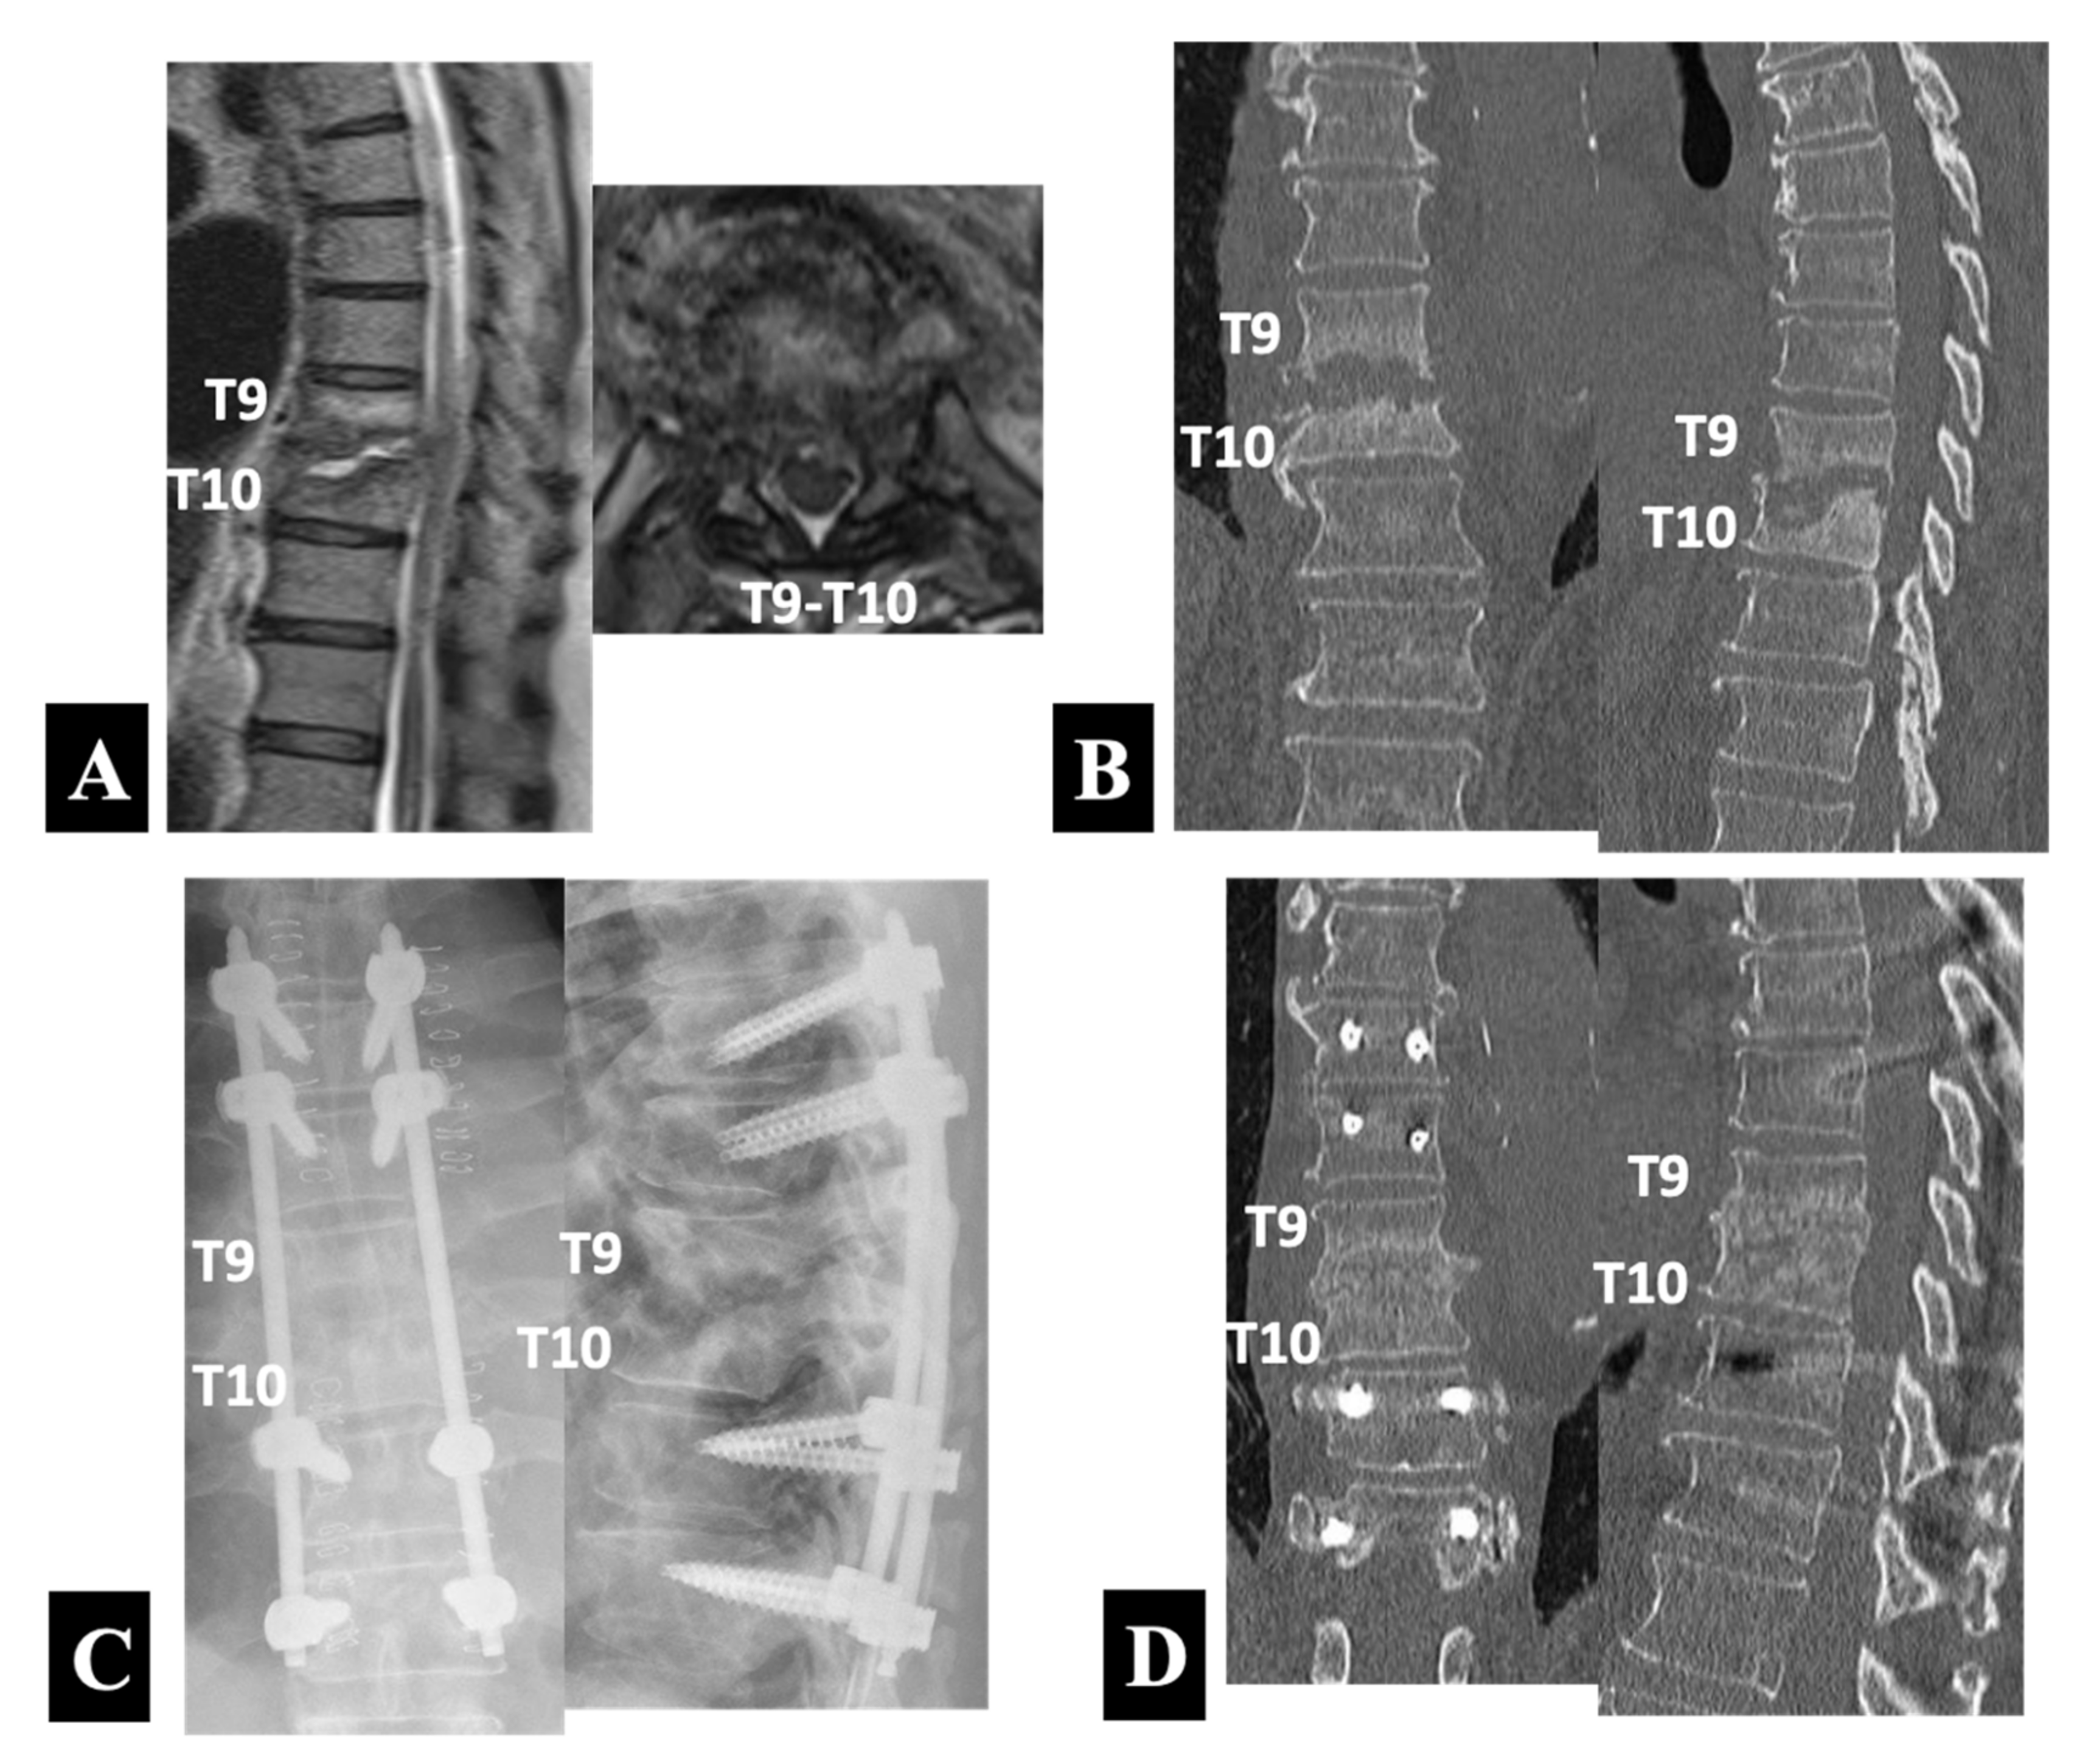

- Case 1 in Group 1-B (Figure 3):